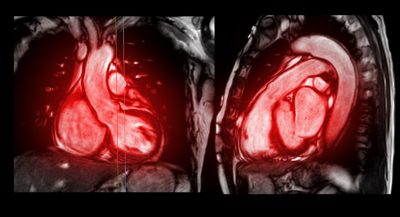

Synopsis: A cardiac magnetic resonance imaging study in a subgroup of the patients in the SUMMIT trial of tirzepatide in patients with heart failure with preserved ejection fraction has demonstrated that patients treated with tirzepatide had reduced left ventricular mass and paracardiac adipose tissue compared to placebo-treated patients, which may partially explain the reduction in heart failure events observed in the main SUMMIT trial.

This cardiac magnetic resonance (CMR) substudy of SUMMIT was designed to elucidate any cardiac structural changes caused by tirzepatide (TZ) therapy in patients with heart failure with preserved ejection fraction (HFpEF). Such patients have been shown to have increased left ventricular (LV) mass and epicardial adipose tissue. Thus, CMR studies at baseline and at the 52-week final visit were included in the SUMMIT trial.

Baseline CMR showed that LV mass and LA volume were higher than reported normal values. At 52 weeks, placebo-corrected LV mass had decreased by a mean of 11 g in the TZ group (P = 0.004) and LV stroke volume by -8 mL (P = 0.011). Changes in LV end diastolic and end systolic volumes and EF were not significant. PAT was significantly reduced in the TZ group (-45 mL, P < 0.001), which was mainly the result of a decrease in pericardial adipose tissue (-43 mL, P < 0.001).